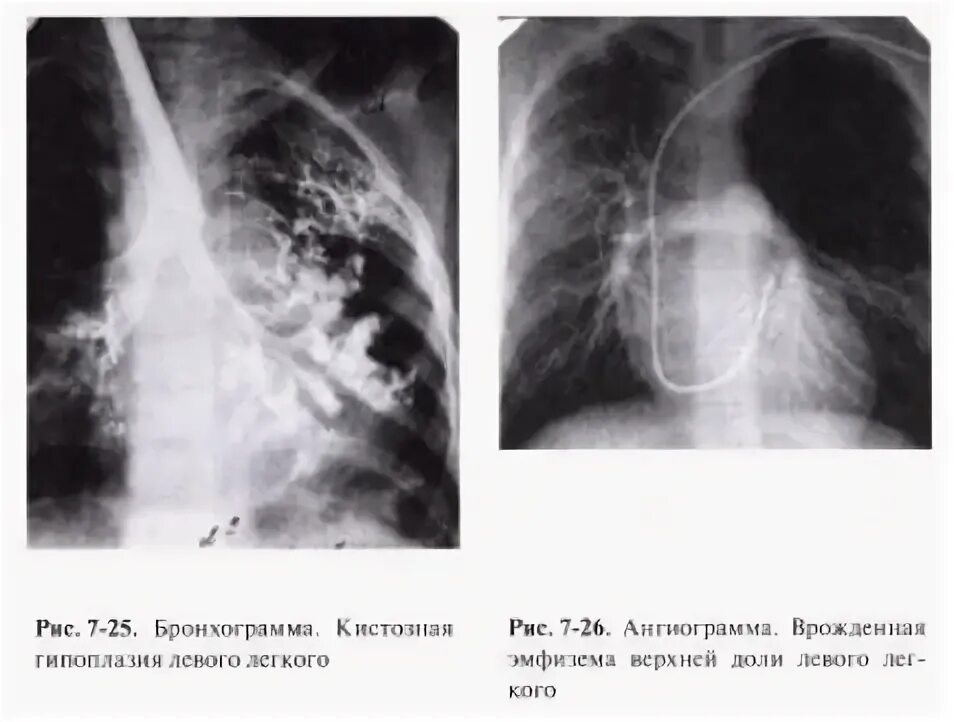

Гипоплазия 12 пары ребер